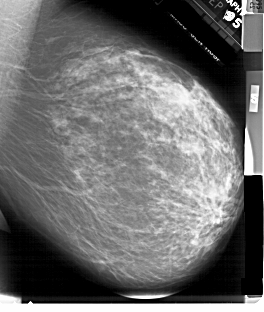

A_1899_1.LEFT_MLO

LESION_TYPE MASS SHAPE IRREGULAR MARGINS SPICULATED

ASSESSMENT 5

SUBTLETY 4

PATHOLOGY MALIGNANT